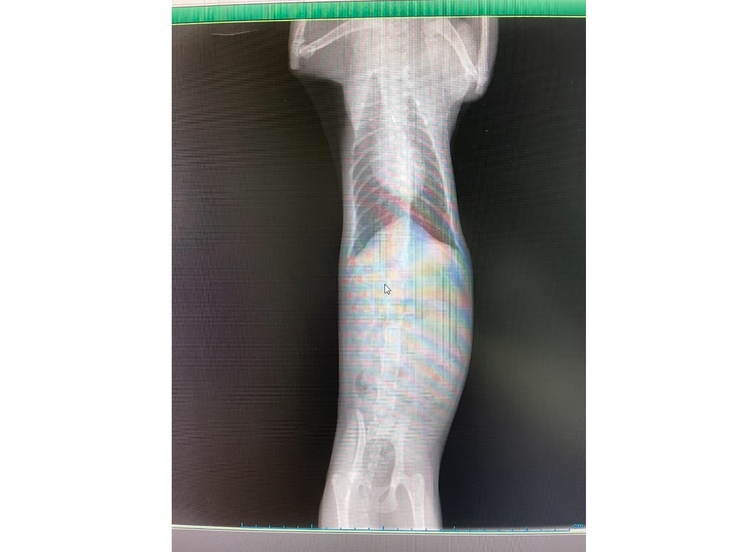

体をグーっと上下に引っ張ってのレントゲンや

○胸部レントゲンでは腹水も見られず良好でしょうとのことでした!